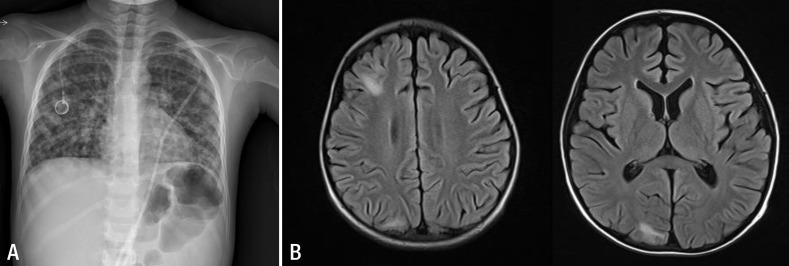

Varicella-zoster virus infection can lead to severe illness in immunocompromised patients. Further the mortality rate of disseminated varicella infection is extremely high particularly in immunocompromised children. We report a case of disseminated varicella infection in a child with acute lymphoblastic leukemia who was receiving chemotherapy, but was initially admitted with only for acute abdominal pain. The patient rapidly developed severe complications, including acute respiratory distress syndrome, acute hepatitis, disseminated intravascular coagulation, and encephalopathy. Acyclovir is a highly potent inhibitor of varicella-zoster virus infection. However, owing to rapid disease progression, it might not be sufficient to control a disseminated varicella infection, especially in immunocompromised patients. Immunoglobulin neutralize virus invasion and suppress viremia, acting synergistically with acyclovir. In this case, early administration of acyclovir and a high-dose of immunoglobulin, combined with mechanical respiratory support, proved adequate for treatment of this severe illness.